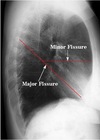

How many fissures separate the lobes of the right lung?

* Two fissures * Minor Fissure - separates RUL and RML * Major Fissure - separates the RUL/RML from the RLL

52

Label 1

* Oblique Fissure

66

Label 2

* Horizontal Fissure